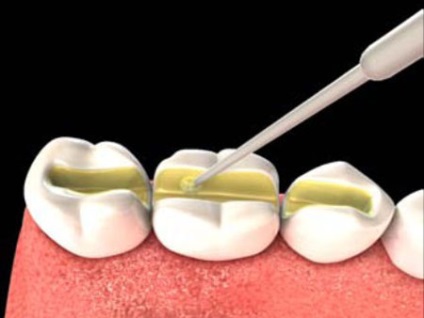

Abroncsok szereléséhez zajlik több lépcsőben. Először szakember teszi a vájat mentén a fogazat be kell zárni egy helyzetben. Ez után jön egy helyi érzéstelenítőt, így sok kellemetlenséget az eljárás nem szállít. Ezután egy hornyot helyezünk a kívánt anyag: üvegszál, aramid-szálból vagy selyem. Ezt követően, az adatok lap bezárásakor tömítést. Ahhoz, hogy a design sima és lapos, az abroncs jól polírozott. Felhívják a figyelmet a képeket, látni fogja a folyamat létrehozása barázdák, amelyek azután elhelyezni munkaanyag. Ebben az esetben, a mélyedés készül a felső oldalon a fogak.